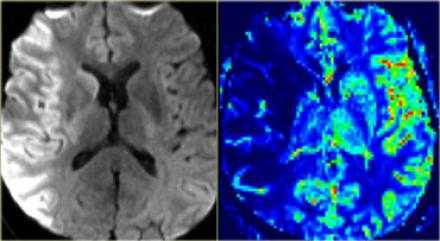

Острая гипертоническая энцефалопатия

Острая гипертоническая энцефалопатия - патологическое состояние, возникающие из-за повышенного артериального давления (АД выше 200/130 мм. ртутного столба, реже при более низком давлении). Характеризуется возникновением участков ишемии в тканях головного мозга, вплоть до образования микроскопических кровоизлияний. В норме при повышении артериального давления происходит спазм мелких артерий головного мозга, однако при острой гипертонической энцефалопатии этот же спазм может стать запредельным, что и приводит к возникновению участков тканей мозга, испытывающих недостаток кислорода. Резкое расширение спазмированных артерий ведет к отеку мозга. Острая гипертоническая энцефалопатия - предвестник геморрагического инсульта.

На МРТ-снимках признаки гипертонической энцефалопатия проявляются в виде множественных очагов ишемии/микроскопических кровоизлияний в тканях головного мозга. В ангио-режиме одновременно обнаруживается спазм одних и расширение других артерий.